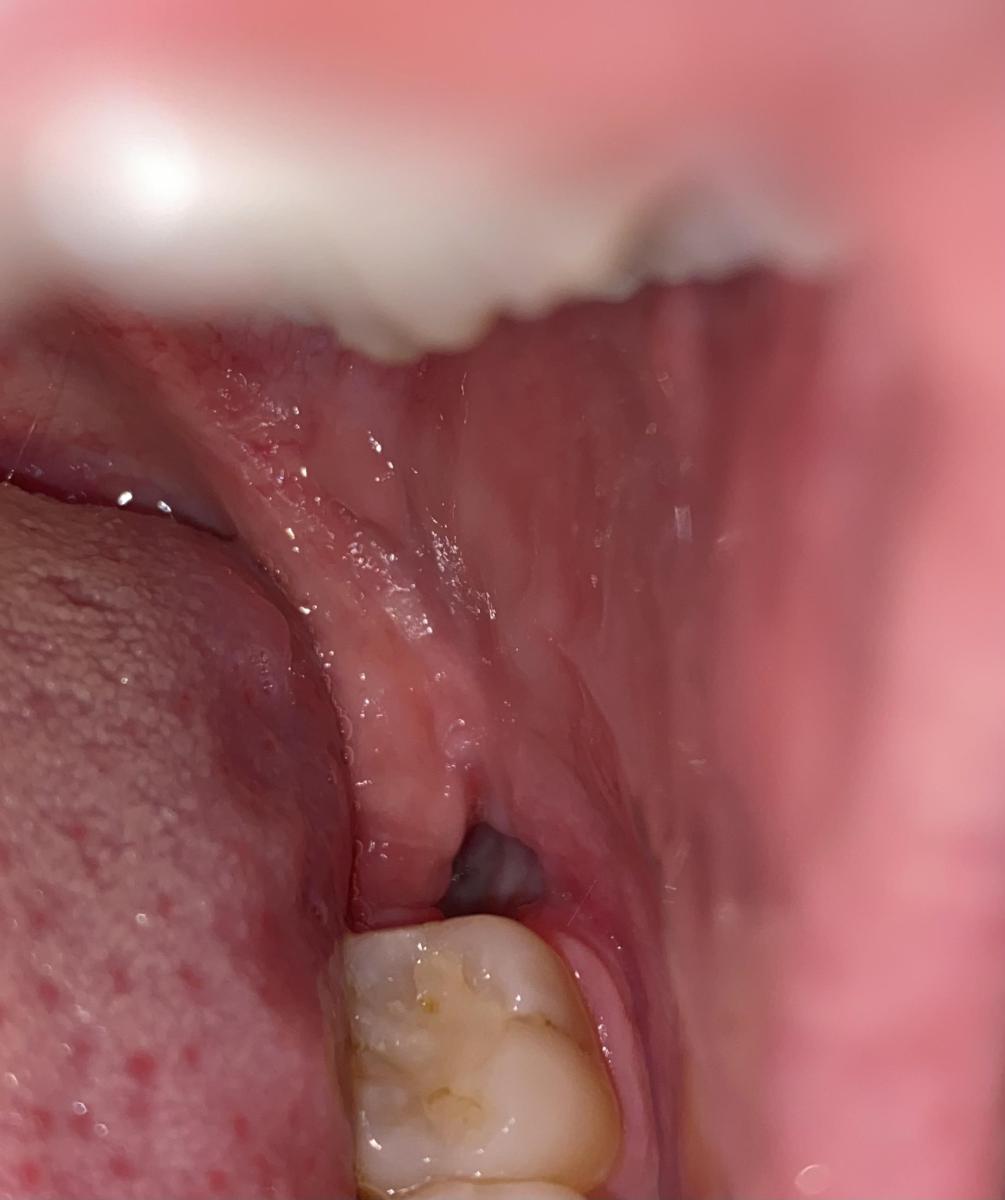

Всем добрый день, недели 2 назад удалили зуб мудрости, нормально заживает или нет не могу понять, удаление было сложным, швы сняли на 8 день, боли нет, иногда ухо немного пульсирует но проходит, обычно ночью и десна на 7 зубе немного припухла, не болит но немножко дискомфорт есть